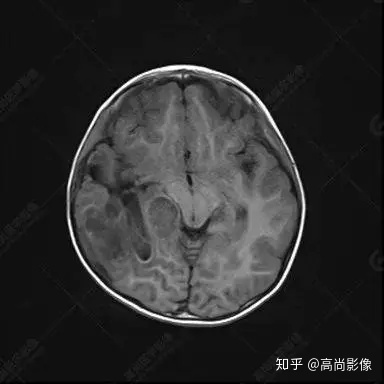

右側(cè)顳葉腫瘤切除術(shù)后(具體不詳):右側(cè)顳部骨質(zhì)不連續(xù)呈術(shù)后改變,右側(cè)顳葉術(shù)區(qū)見片狀長(zhǎng)T1長(zhǎng)T2信號(hào)影,F(xiàn)LAIR呈低信號(hào);術(shù)區(qū)后方右側(cè)顳枕葉見一巨大占位性病變影,邊界欠清,大小約6.2×5.8×4.3cm(前后×左右×上下),信號(hào)不均勻,T1WI呈等稍低信號(hào)間雜少許高信號(hào),T2WI呈高稍低混雜信號(hào),DWI示部分病灶彌散受限,相應(yīng)ADC圖減低,磁敏感序列見部分呈極低信號(hào),增強(qiáng)掃描可見明顯不均勻強(qiáng)化,鄰近硬腦膜及小腦幕增厚并明顯強(qiáng)化;另延髓右前方及右側(cè)橋小腦角區(qū)見一不規(guī)則形異常信號(hào)影,大小約3.2×1.3×3.7cm(左右×前后×上下),呈長(zhǎng)T1稍長(zhǎng)T2信號(hào),F(xiàn)LAIR呈等信號(hào),DWI未見受限,增強(qiáng)后明顯均勻強(qiáng)化,鄰近腦膜明顯強(qiáng)化。鄰近腦實(shí)質(zhì)及右側(cè)顳角明顯受壓;左側(cè)大腦半球未見局灶性信號(hào)異常,中線結(jié)構(gòu)稍左移。

右側(cè)顳葉腫瘤切除術(shù)后:現(xiàn)術(shù)區(qū)后方右側(cè)顳枕葉及延髓右前方占位,右側(cè)顳枕部硬腦膜及小腦幕明顯強(qiáng)化,結(jié)合既往影像資料,考慮為胚胎源性惡性腫瘤,如非典型畸胎樣/橫紋肌樣瘤(AT/RT)或原始神經(jīng)外胚層腫瘤(PNET)。